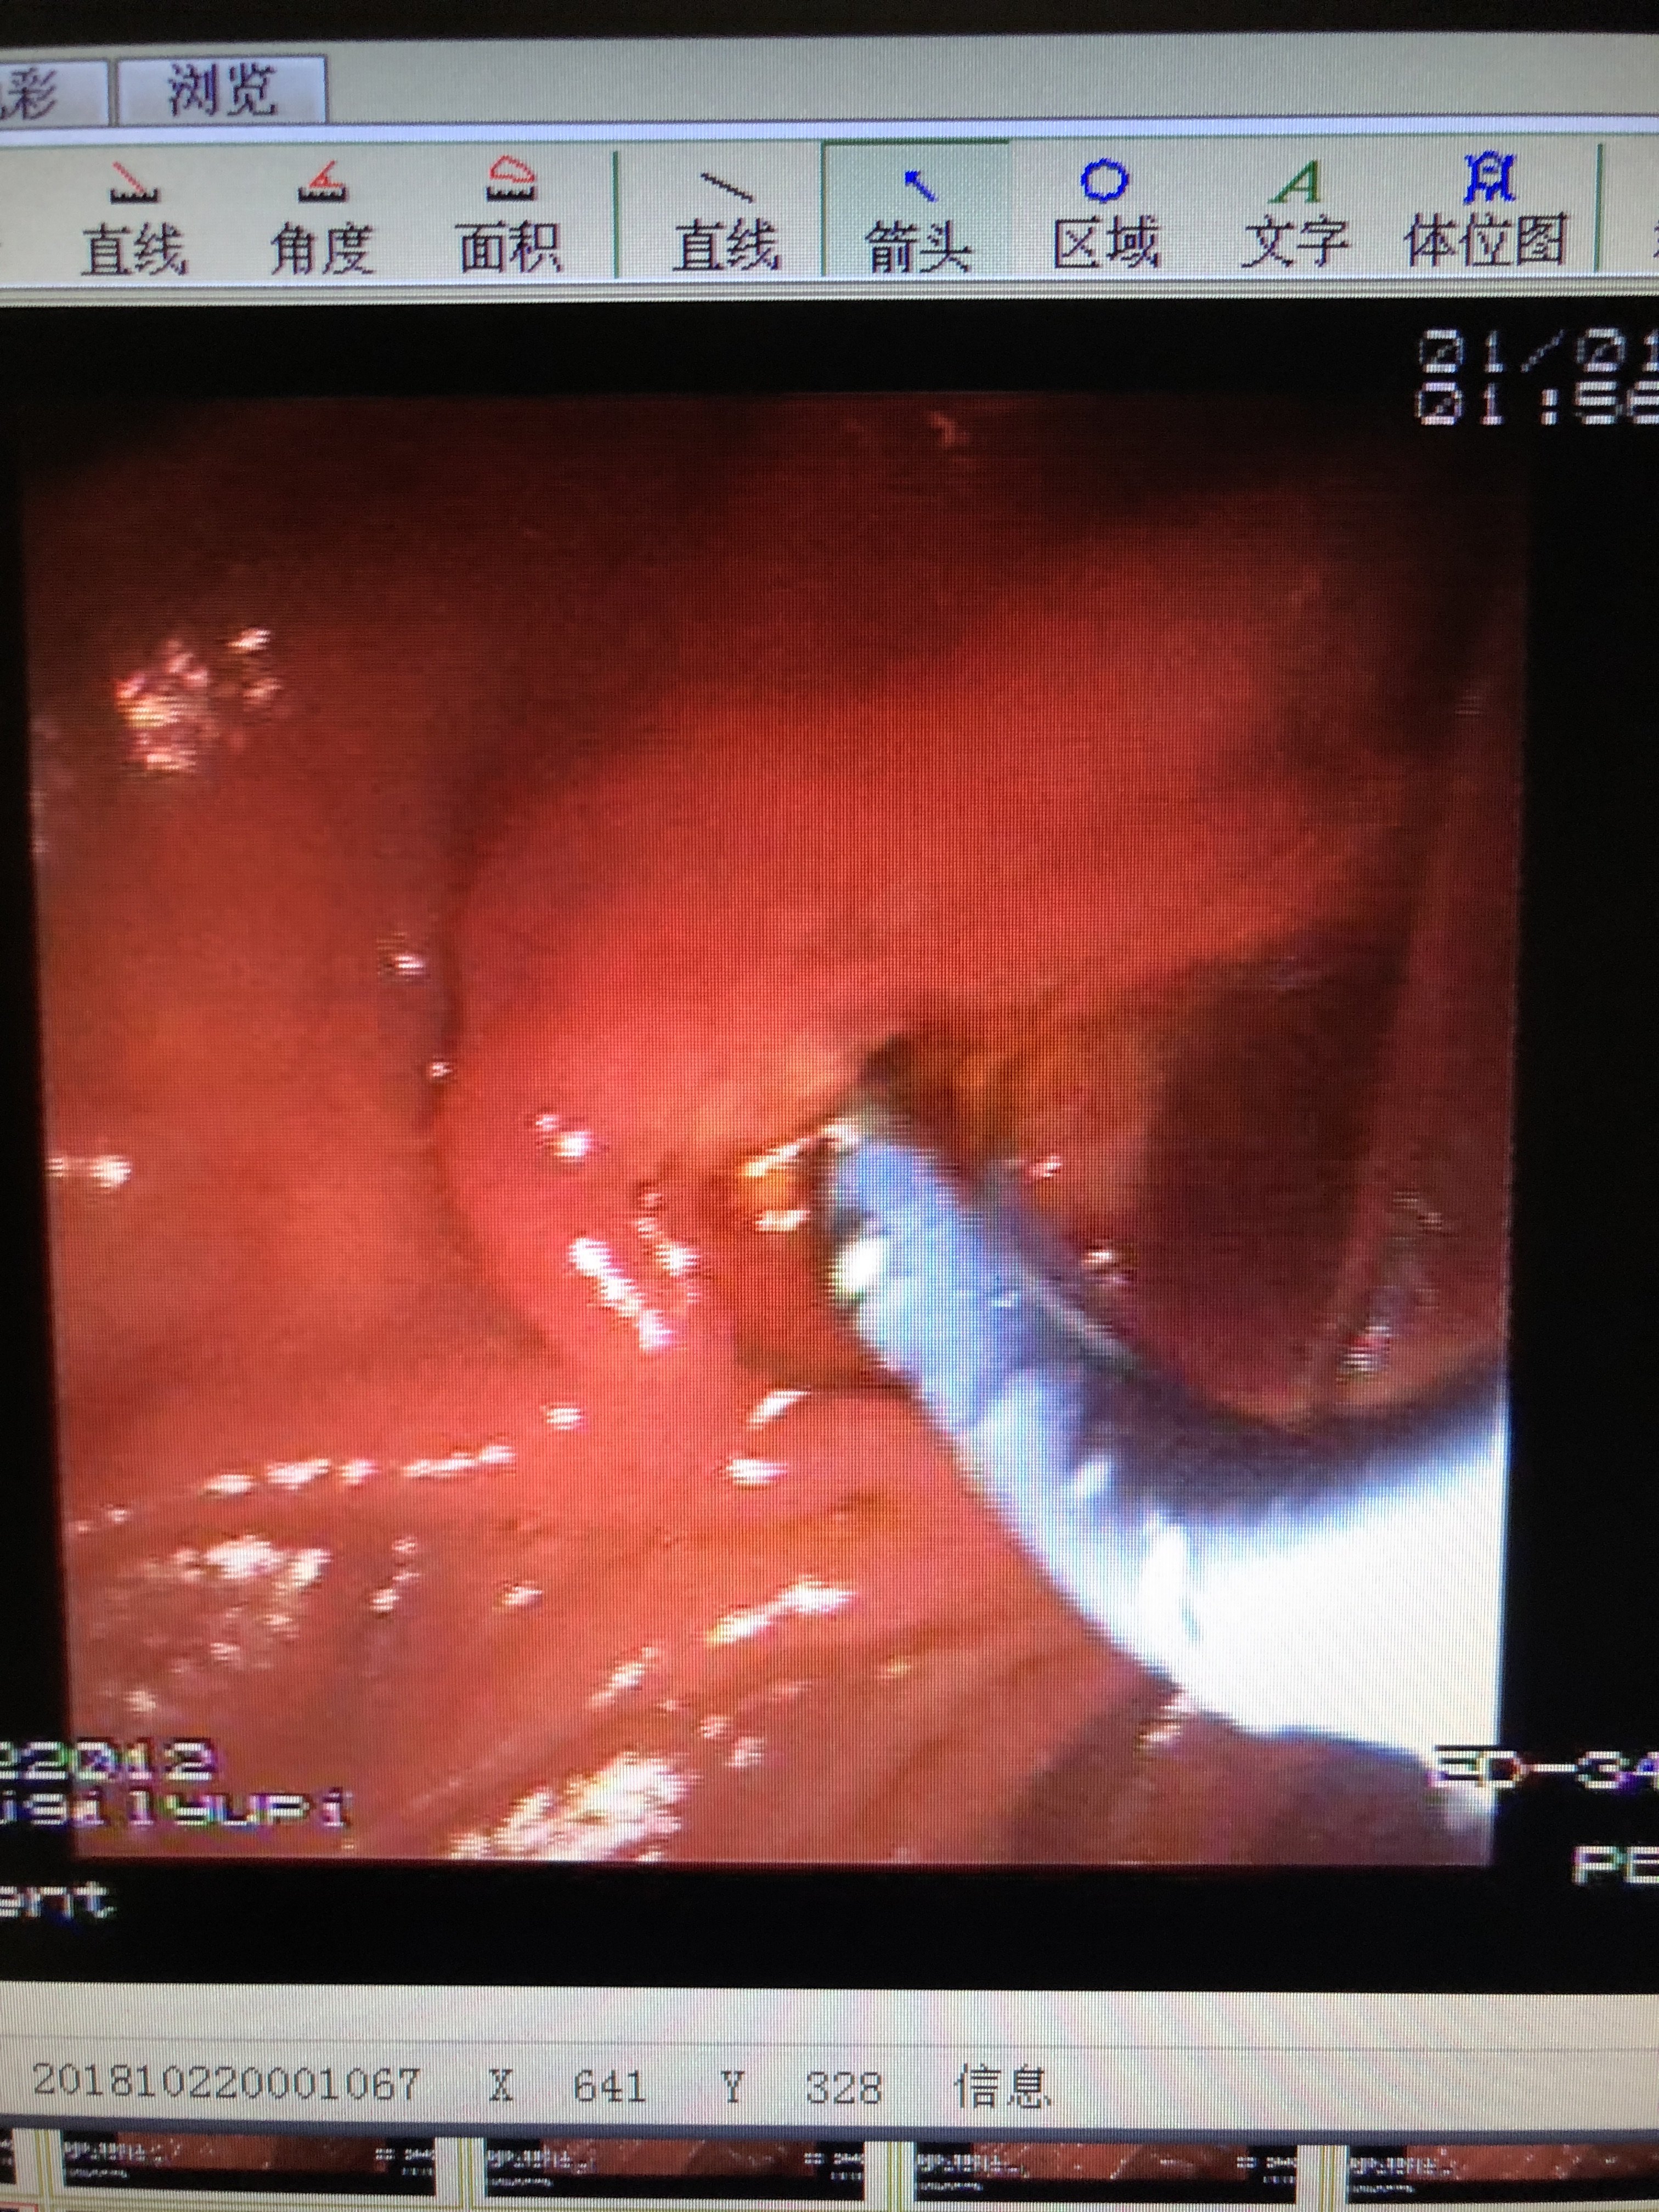

胆管下端狭窄即缩窄性乳头炎伴胆管扩张并

3024x4032 - 1480KB - JPEG